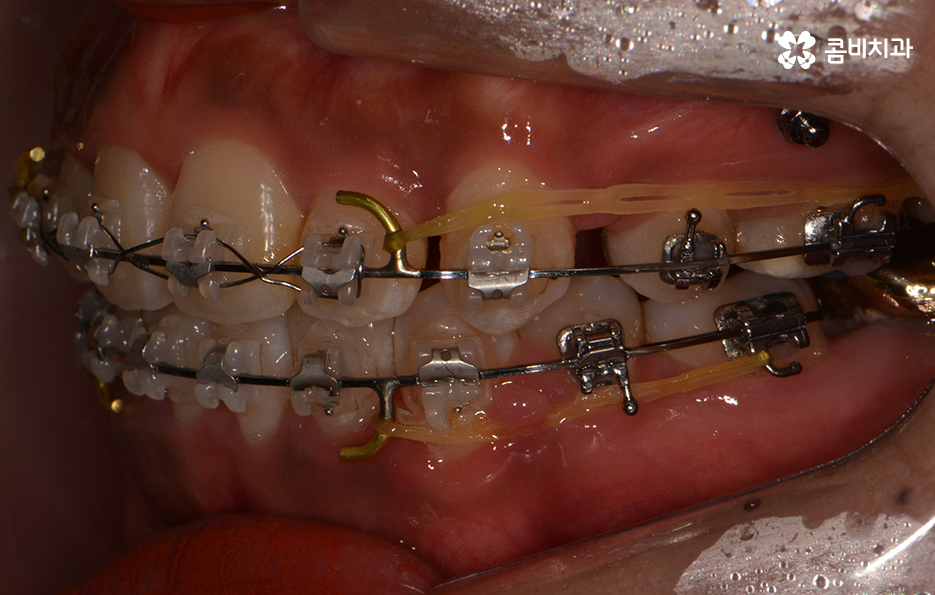

교정이 시작된 후 경과 - 발치를 했던 부위의 치아 사이 빈 공간이 사라짐

바쁜 직장인 분들의 경우 주기적인 내원에 대한 부담감을

더 크게 느낄 수밖에 없고 일상생활을 하면서

느끼는 관리상의 효율과 편의성에 대한 부분도 중요하게 느끼실 텐데요.

클리피씨교정은 관리의 용이함은 물론이며 주기적으로

내원을 해야 하는 횟수를 줄일 수 있다는 점에서도

바쁘거나 상황적으로 제약이 있으신 경우 많이 선호합니다.